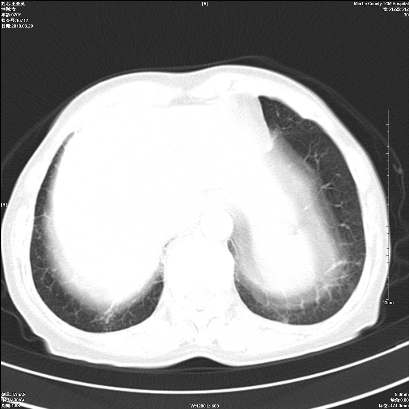

右肺上叶支气管开口阻塞,上叶呈不均匀致密影,右肺中下叶内见斑片状密度增高影,上叶见钙化点,纵隔内见钙化淋巴结,桶状胸,右下肺动脉增粗,残根征,意见:1.右肺中心性肺癌;2.右肺陈旧性结核;3.肺心病。

1)考虑右肺中央型肺癌伴右肺上叶肺不张,右肺门淋巴结转移;建议行支纤维镜检查。2)右肺中叶、下叶及左肺上叶舌段感染性病变。3)肝内多发低密度影,不排除转移瘤可能;建议行ct增强扫描检查。

ct所见:右肺上叶肺不张,呈软组织密度影向肺门区聚拢,其内可见含气段支气管及细支气管影,病灶内尚可见钙化结节。右肺上叶支气管狭窄,段支气管壁可见钙化。右肺下叶背段、右肺中叶见不规则小片絮状影及纤维条索影,形态较僵硬。右肺中叶胸膜旁可见多个小结节影。纵膈内见钙化淋巴结。

分析:右侧胸廓及右肺体积缩小,说明病变时间比较长了,应该是有数年的时间了,如果是短期内出现的肺不张,只会引起纵膈向患侧移位,而不会引起胸廓的塌陷。不张的肺组织内可见含气支气管影,说明右肺上叶支气管没有完全中断,只是狭窄。右肺中叶、下叶散在不规则病灶,部分呈纤维化改变。纵膈内的淋巴结大部分钙化。因此,本例给我的感觉良性病变的可能是大。